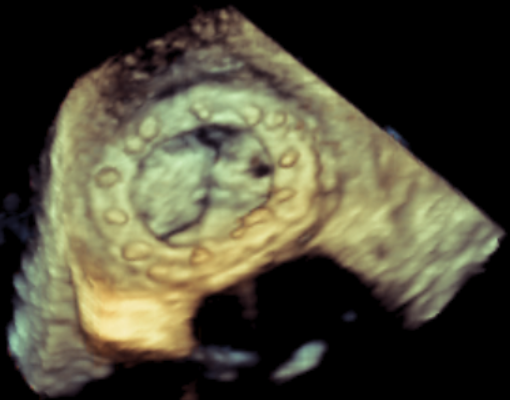

收缩期未见瓣周漏

左房内未见对比剂显影